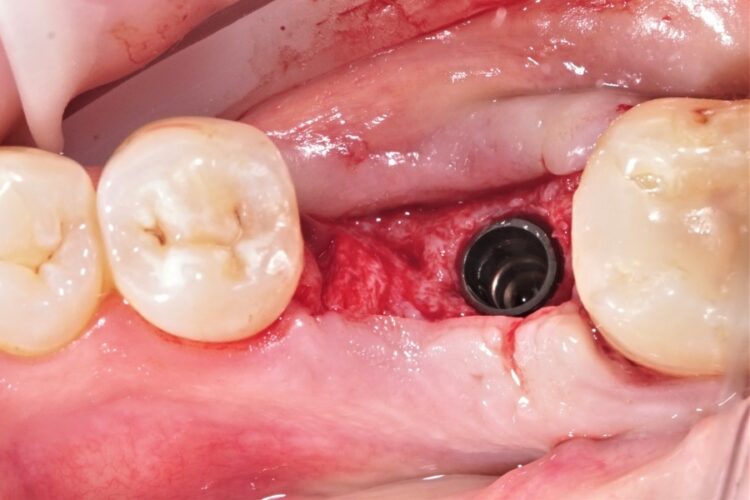

Клинический кейс имплантации

Все этапы: от компьютерной томограммы до установки коронки на имплант.

Установленный имплант: 4.5 мм на 11.5 мм

Коронка на имплант: дисиликат лития, винтовая фиксация, изготовлена в клинике за 3 часа.

Абатмент: индивидуальный титановый.

Длительность имплантации: 1.5 часа.

Промежуток от импланта до коронки: 3 месяца.

Заключение: проведена установка импланта с одновременной пластикой десны и формированием межзубных сосочков. В имплант установлен формирователь десны. Рана ушита. Швы необходимо снять через 10-14 дней. Даны рекомендации в послеоперационный период.

Установка коронки на имплант запланирована через 3 месяца.

3. Установка самого импланта. Это безболезненная процедура, которая проводится под местным обезболиванием (обезболивается только участок челюсти на котором проводится хирургическое вмешательство). Наркоз или седация целесообразны при установке большого количества имплантов с проведением сопутствующих операций или при патологической боязни пациента, или наличии сопутствующих заболеваний.

Этапы:

- Разрез слизистой для обеспечения доступа к костной ткани альвеолярного отростка.

- С помощью аппарата (который называется физиодиспенсер) и различных по диаметру и длине сверл создается ложе в кости для импланта. Очень важно, чтобы работа на кости проводилась на специальном имплантологическом оборудовании. Особенностями которого является обеспечение охлаждения кости в процессе работы и наличие определенных режимов работы.

- В подготовленное ложе устанавливают имплант. Он должен быть установлен полностью в костную ткань и закрыт заглушкой. Одновременно с установкой импланта возможно проведение подсадки костной ткани, мембран, PRF сгустков. PRF - это фибрин обогащенный тромбоцитами; его получают из венозной крови пациента после обработки в специальной центрифуге (в стоматологической клинике iStomatolog применяют центрифугу DUO by dr. Joseph Choukroun). Благодаря наличию большого количества факторов роста в PRF сгустках и мембранах - улучшается приживление импланта, сокращается срок восстановления слизистой оболочки десны и костной ткани; значительно снижается вероятность возникновения осложнений после имплантации. Данную технологию еще называют плазмолифтингом и применяют с целью омоложения кожи.

- Ушивание слизистой над установленным имплантом. Нитки, которые используют могут быть рассасывающимися, то есть нет необходимости снятия швов, и нерассасывающиеся - доктор предупреждает через сколько дней пациенту необходимо снять швы.